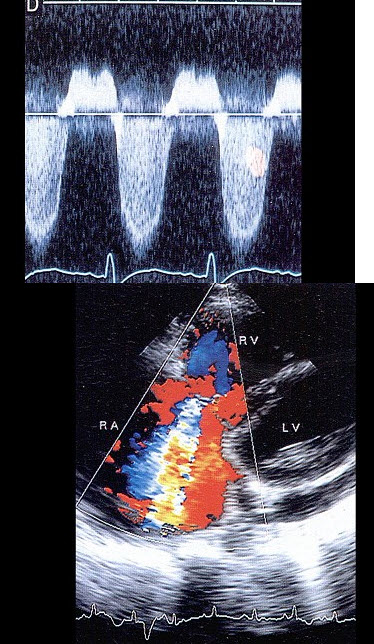

19、单项选择题 患者下肢水肿、心悸,该病例诊断最可能是()

A.心包积液

B.心包缩窄

C.心包肿瘤

D.室壁瘤

E.限制性心肌病

20、单项选择题 用哪种探头可提高轴向分辨力()